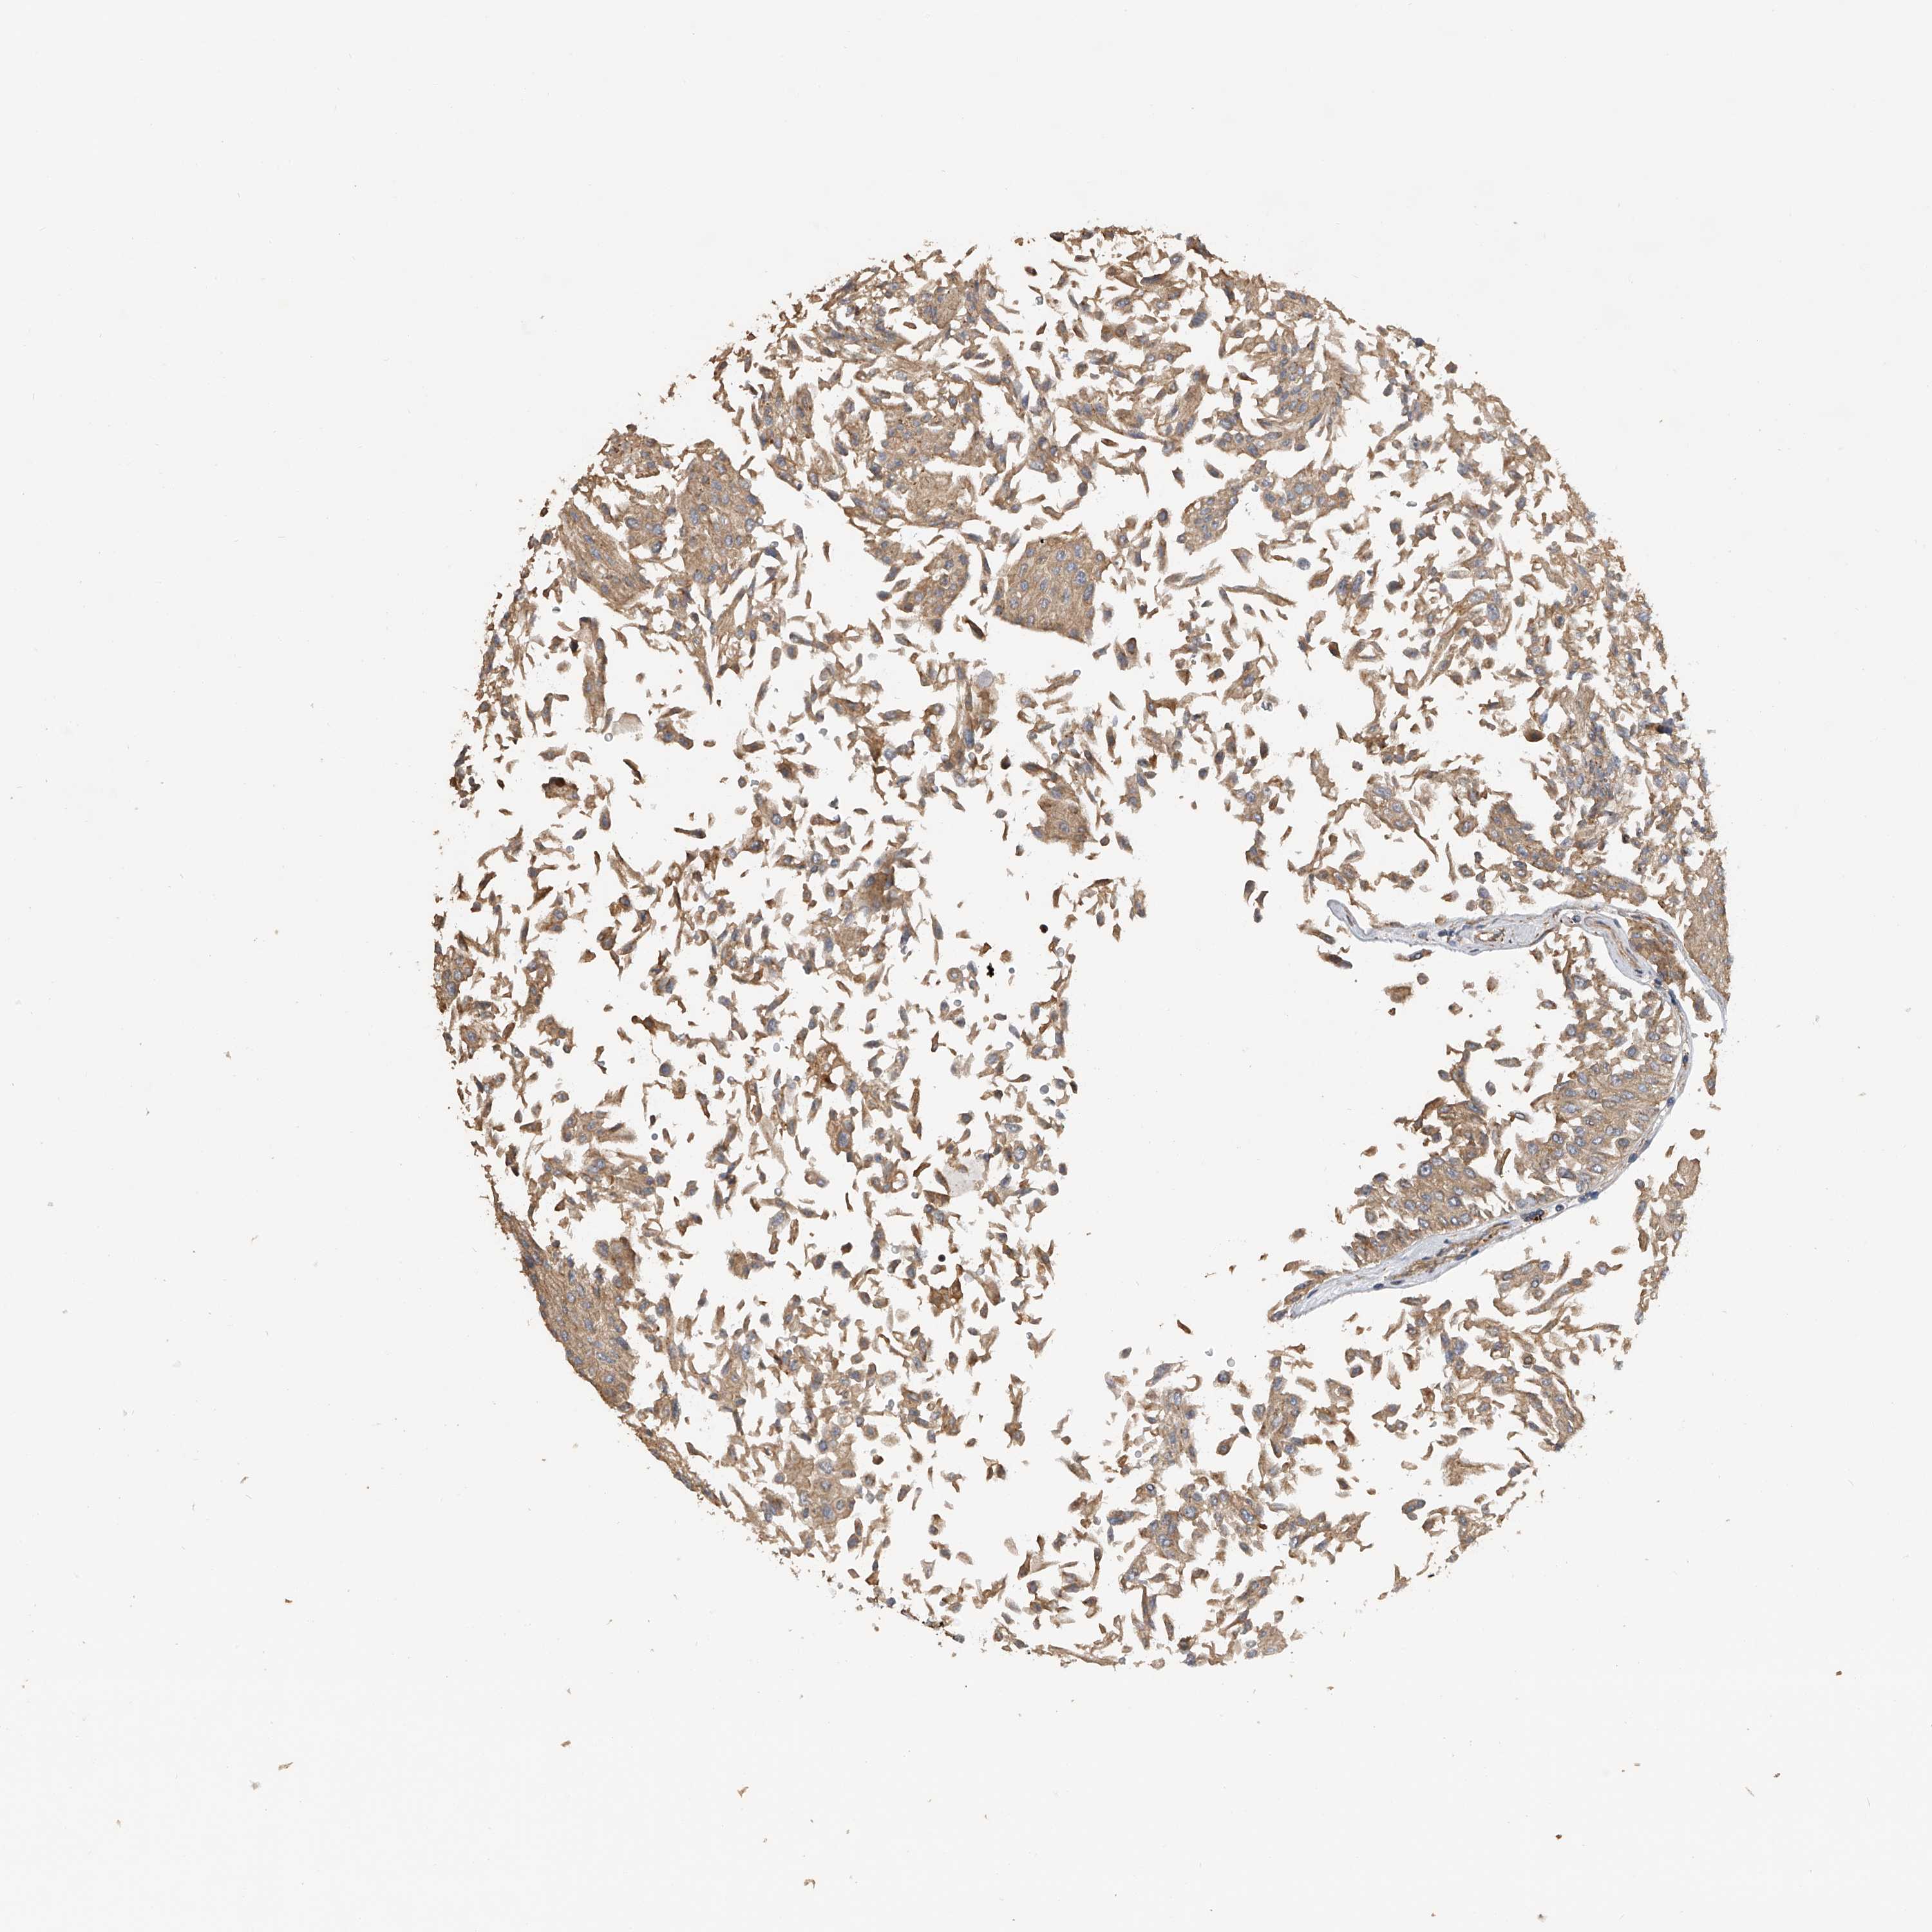

UROTHELIAL CANCER - Protein expressioni

A mouse-over function shows sample information and annotation data. Click on an image to view it in a full screen mode. Samples can be filtered based on level of antibody staining by selecting one or several of the following categories: high, medium, low and not detected. The assay and annotation is described here.

Note that samples used for immunohistochemistry by the Human Protein Atlas do not correspond to samples in the TCGA dataset.

Antibody stainingi

Antibody staining in the annotated cell types in the current human tissue is reported as not detected, low, medium, or high, based on conventional immunohistochemistry profiling in selected tissues. This score is based on the combination of the staining intensity and fraction of stained cells.

Each image is clickable and will lead to virtual microscopy that enables deeper exploration of all samples and also displays staining intensity scores, fraction scores and subcellular localization as well as patient and tissue information for each sample.

Antibody HPA029412

Antibody CAB034366

Urothelial carcinoma, Low grade

Urothelial carcinoma, High grade